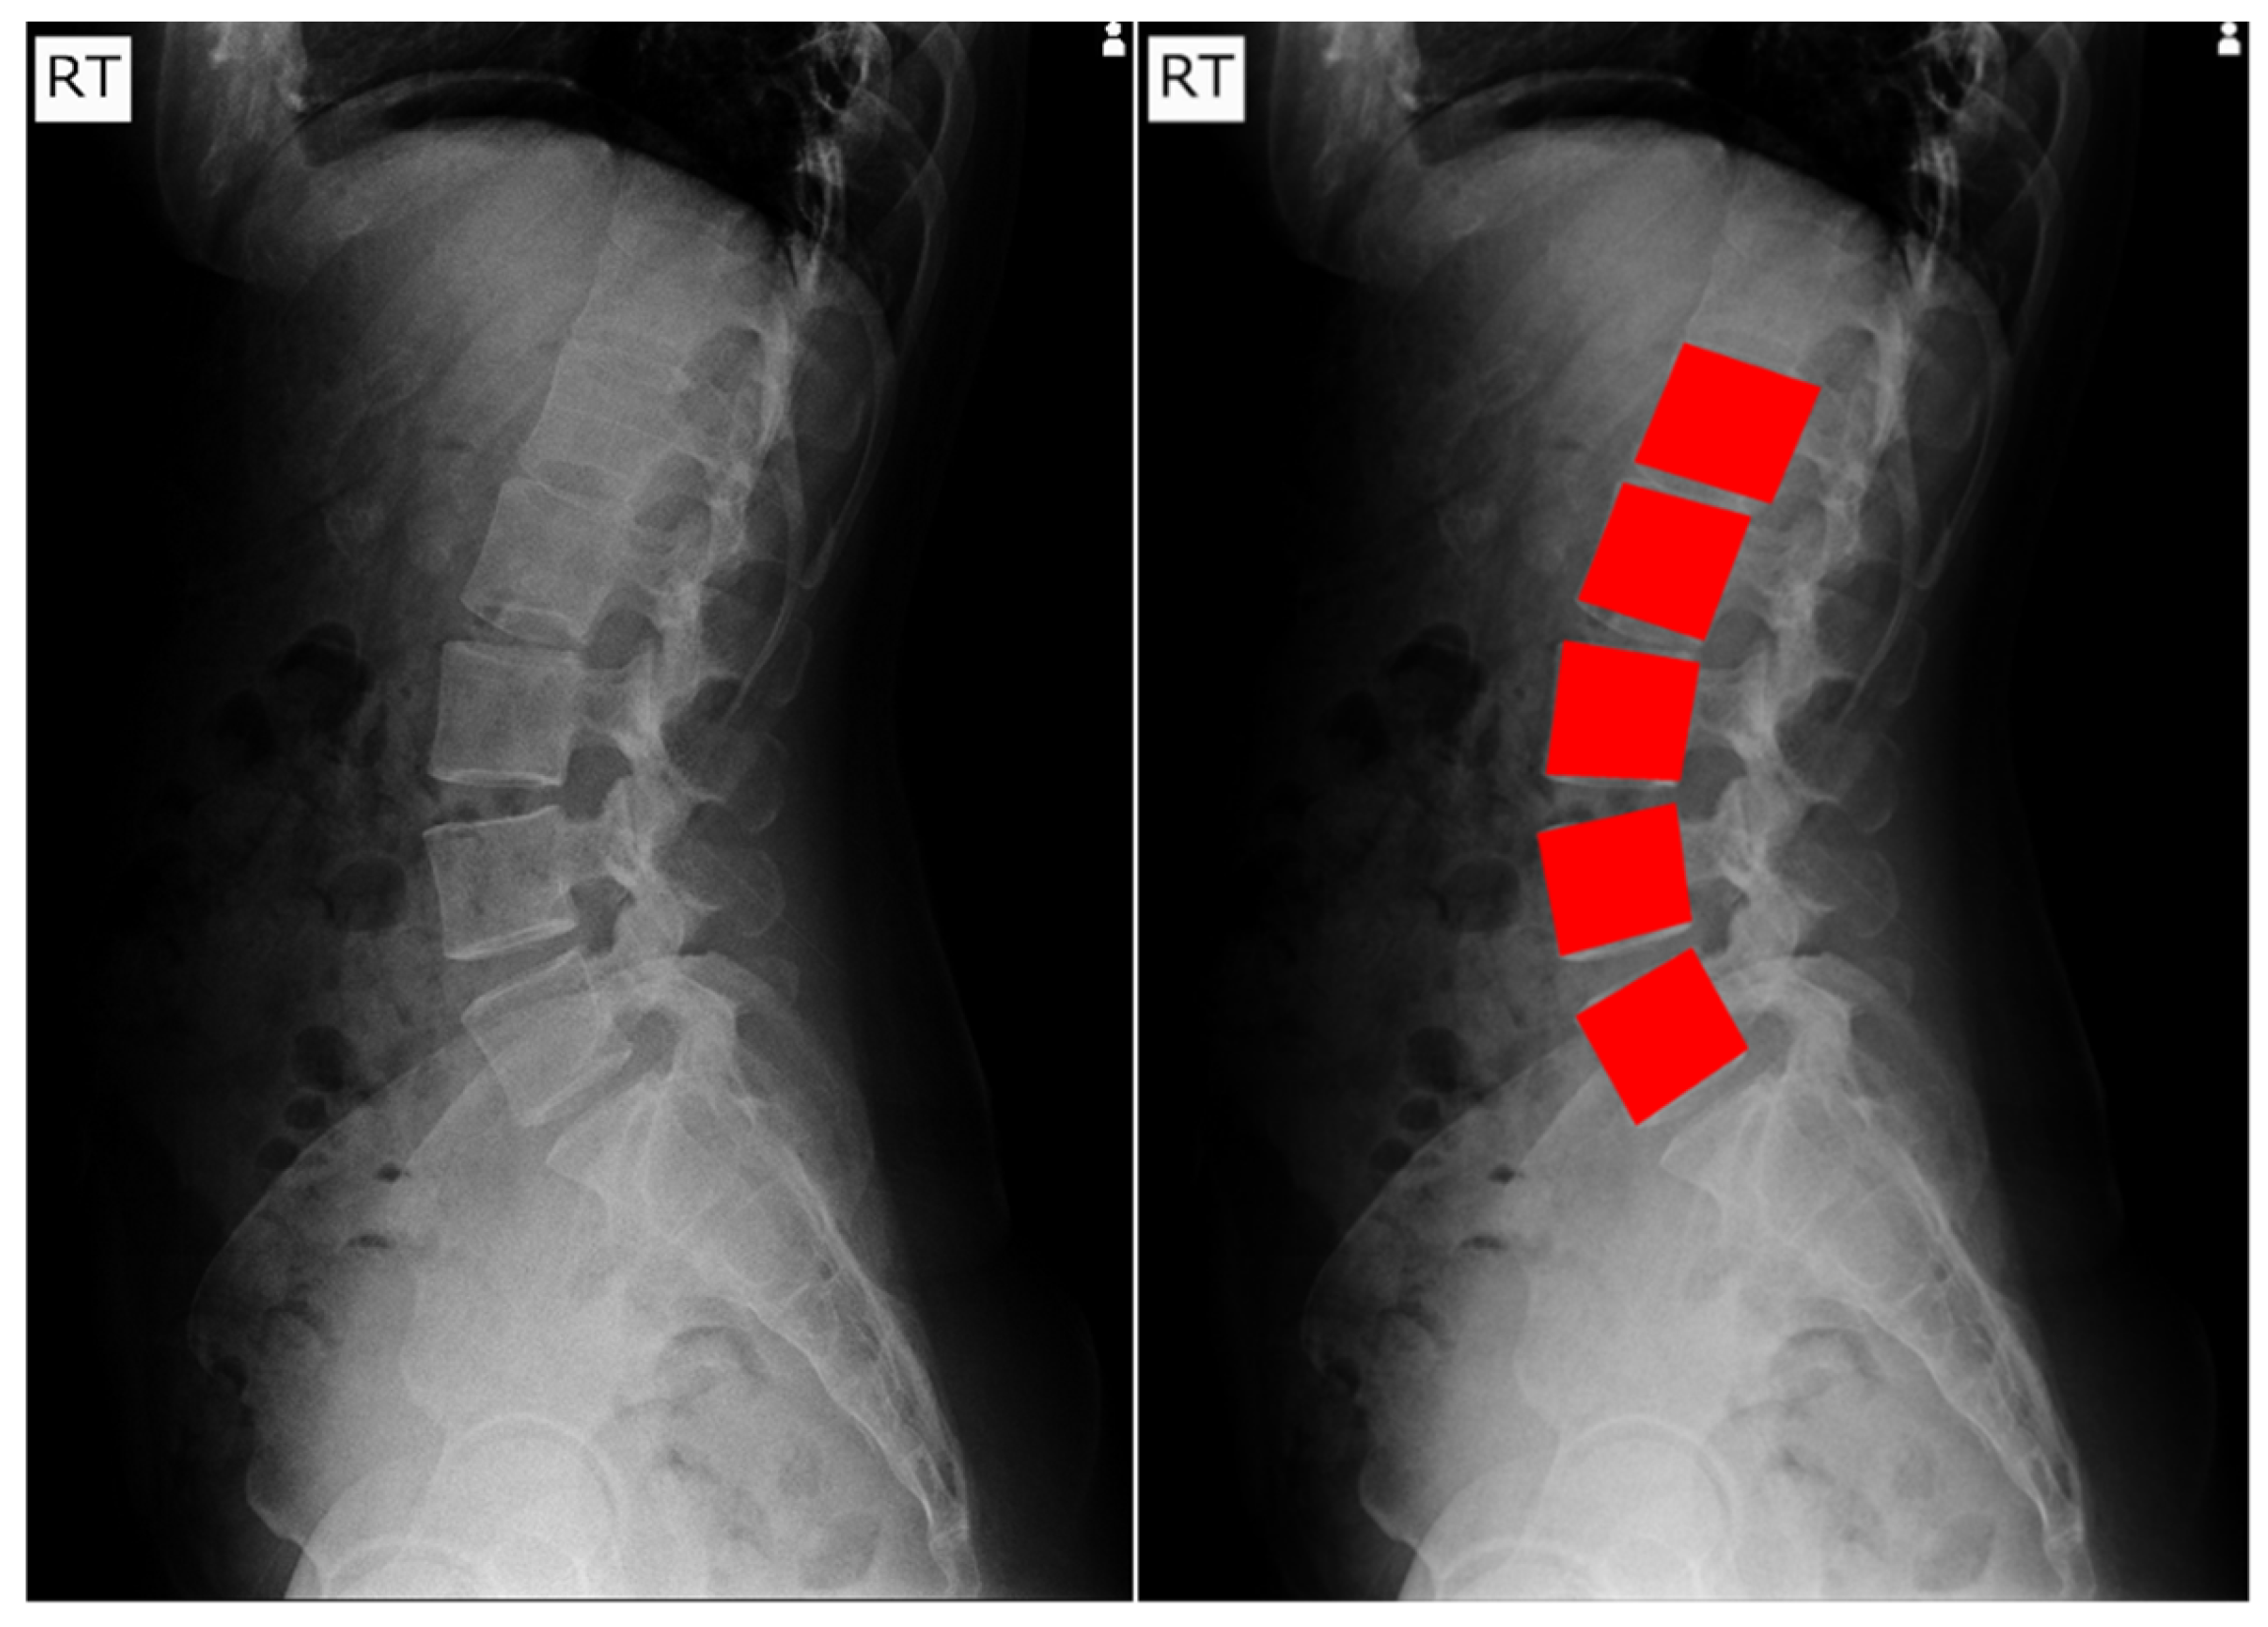

A representative image from the test dataset is selected to evaluate the model’s robustness under challenging conditions, characterized by low contrast and grain noise. As displayed in

Figure 11, the segmentation prediction is visualized for each spine segment using different colors. All the Mask R-CNN configurations successfully locate and segment the lower lumbar region (L3, L4, and L5). The application of enhancement methods notably improved performance in the upper lumbar region (L1 and L2). All models using enhanced images correctly predicted L2, and all contrast-enhancement techniques, CLAHE and HE, led to the models successfully segmenting L1. A distinct advantage of TL is observed with AD, where the TL Mask R-CNN correctly identified L1, while the scratch model failed to localize this segment.

Without enhancement, the Mask R-CNN struggles to differentiate the upper vertebrae (L1 and L2). Scratch Mask R-CNN displaying overlapping segmentation errors on the L2 spine segment. Even though the unenhanced TL model correctly labeled the actual L2, it produces a duplicate prediction, mistakenly labeling the L1 as L2. Due to this error, the model misidentified T12 (the lowest thoracic vertebra) as L1.

In contrast, the U-Net segmentation result exhibited significantly inferior performance to Mask R-CNN. Even though U-Net configurations successfully segment the L5, the models failed to consistently segment the remaining vertebrae. For L4, there exists a small area of overlap with neighboring spine segments for AD, CLAHE, and HE. In HE, the model struggles to produce the L4 segment, with L5 prediction overlaps. For upper vertebrae (L1, L2, and L3), the U-Net managed only partial and fragmented predictions.